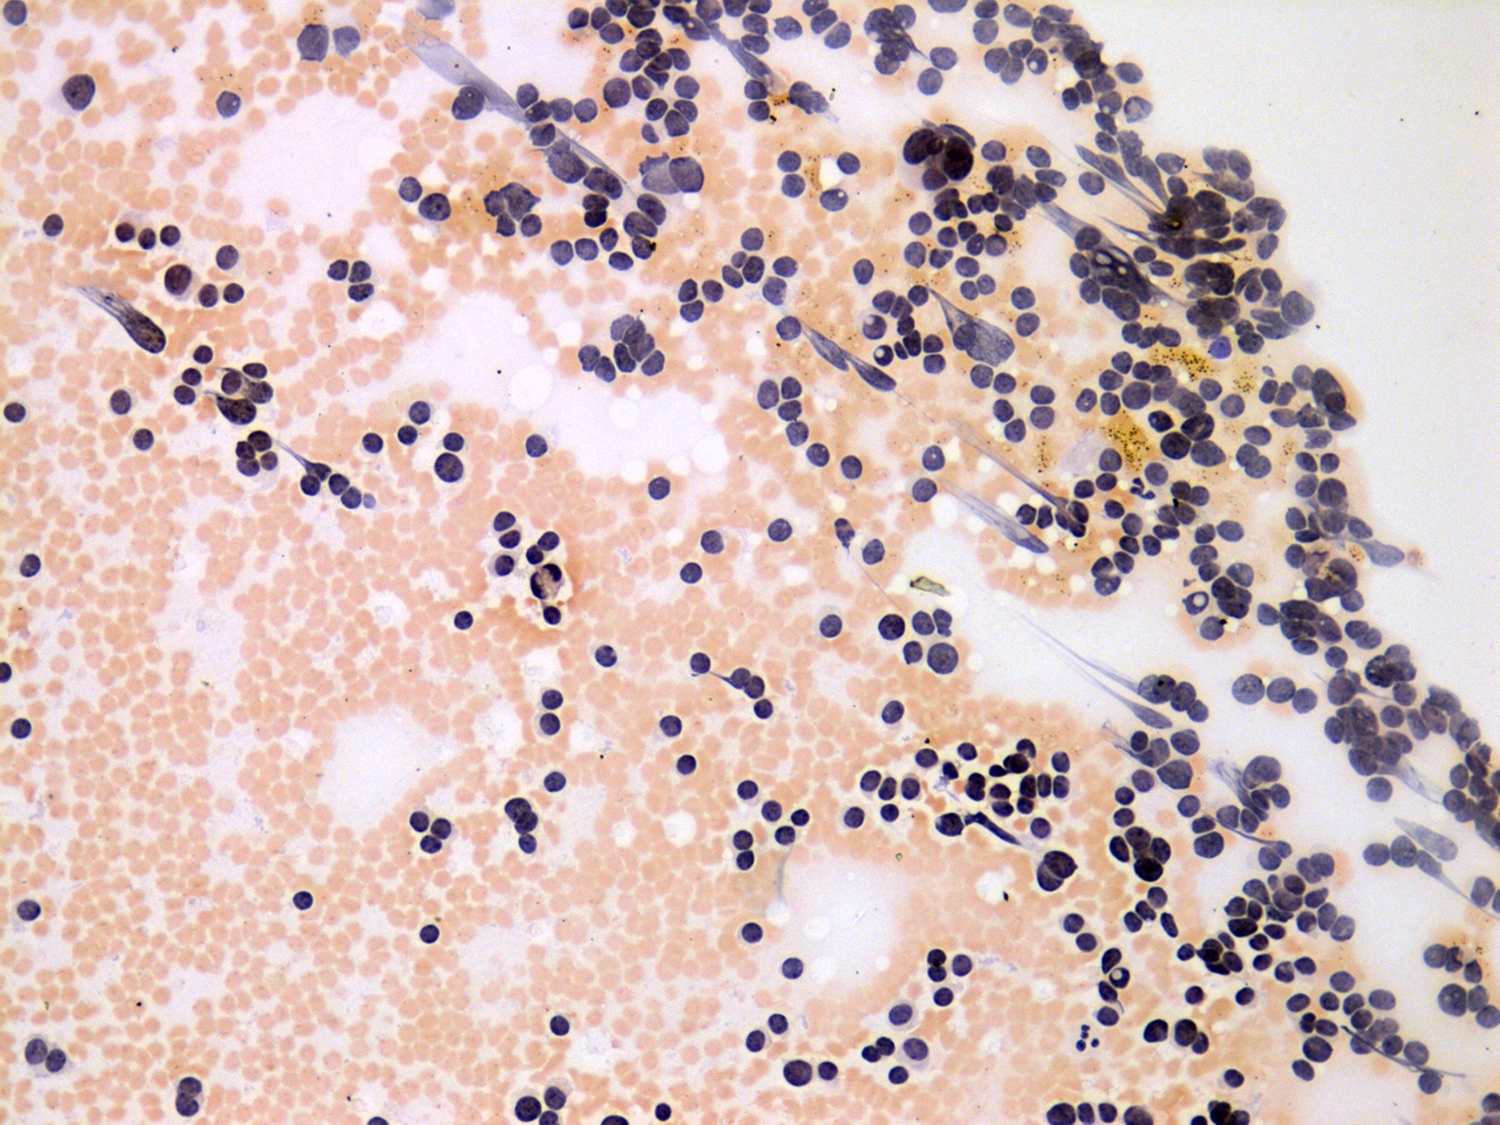

Second examination 4 years later (cytologic picture 2)

Pap-smear, 200x. Several enlarged atypical cells are found.